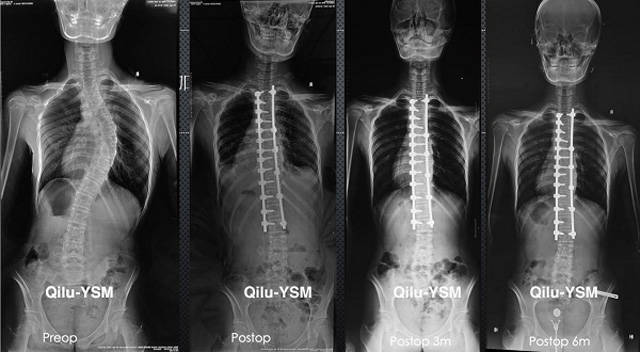

懸吊DR-全電動(dòng)型機(jī)架DR檢查主要用于胸部、四肢、關(guān)節(jié)、脊柱等,主要檢查肺部炎癥、腫瘤、結(jié)核病、四肢骨關(guān)節(jié)的骨折、四肢關(guān)節(jié)、脊柱外傷等。DR就是X光,是一種數(shù)碼影像,曝光時(shí)間很短,攝像量很小,影像質(zhì)量也很好,可以說(shuō)是一種替代CR的方法。DR檢查有其局限性,需要做CT平掃等檢查,周?chē)馨徒Y(jié)的轉(zhuǎn)移以確定病變的良惡性、范圍、大小、與鄰近組織的關(guān)系。